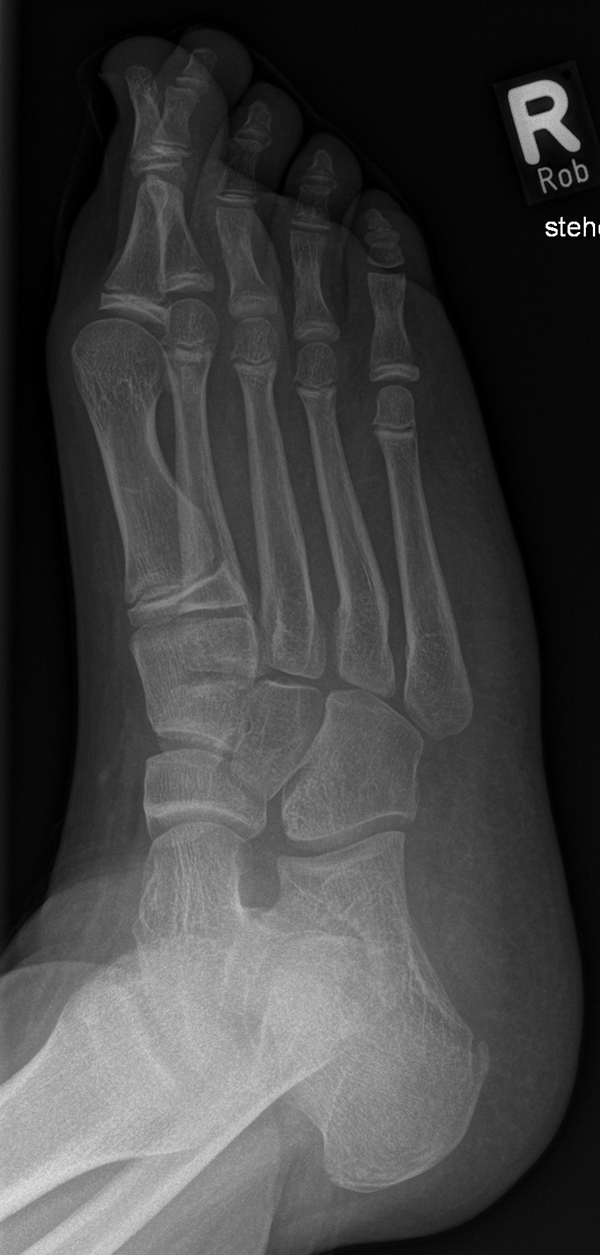

Diagnostisches Vorgehen

Damit die minimalinvasive Fußchirurgie zur Korrektur kindlicher oder jugendlicher Fußdeformitäten erfolgreich angewendet werden kann, erfordert die präoperative Diagnostik Röntgenbilder in drei Ebenen am stehenden Fuß. Röntgenbilder ohne Belastung des Fußes sind nicht zielführend. Im Fall von schweren Rückfußdeformitäten wird das obere Sprunggelenk in die radiologische Diagnostik mit einbezogen in Kombination mit der Rückfußaufnahme unter Belastung („Saltzman View“). Das OSG wird in zwei Ebenen geröntgt. Die streng seitliche Aufnahme des OSG kann bei den komplexen Fußdeformitäten mit der seitlichen Aufnahme des Fußes unter Belastung kombiniert werden. Das reduziert die diagnostische Strahlenbelastung der Kinder.

Indikationen für die beschriebenen Röntgenaufnahmen sind Klumpfußdeformitäten zur Beurteilung eines „flat top talus“ oder neurologische Grunderkrankungen mit varischer Fersenstellung wie zum Beispiel bei HSMN (Hereditäre Sensorische Motorische Neuropathie).